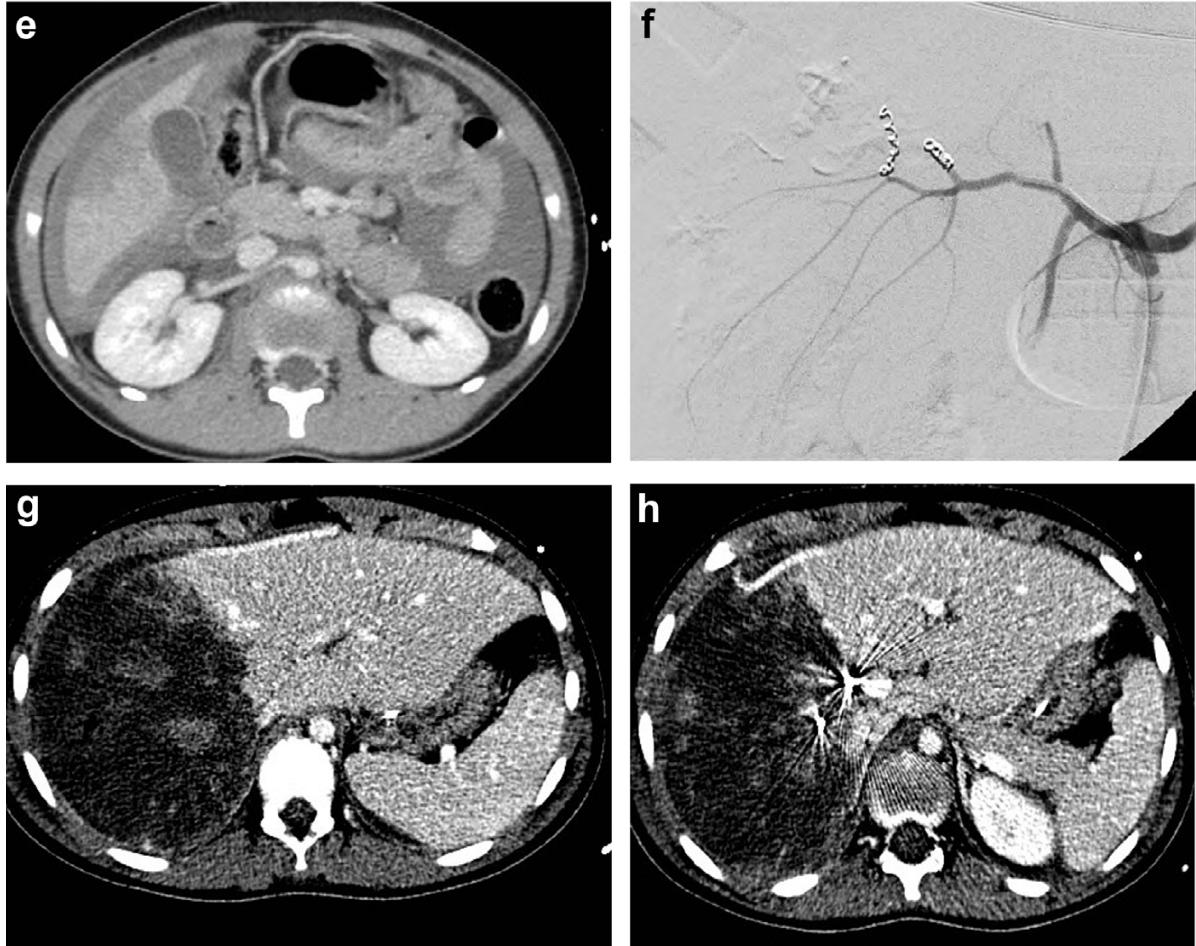

肝脏损伤4度

肝脏损伤介入治疗

损伤部位标记

5.1. 肝损伤在CT扫描中诊断,从1级到IV级损伤,生命体征稳定,同时:a)损伤未累及肝门。b)肝周血肿比较局限。

- Liver injury diagnosed on CT scan with normalizing vital signs Grade I to IV: a) Injury not into hilum.b) Rim of blood fairly localized around liver.